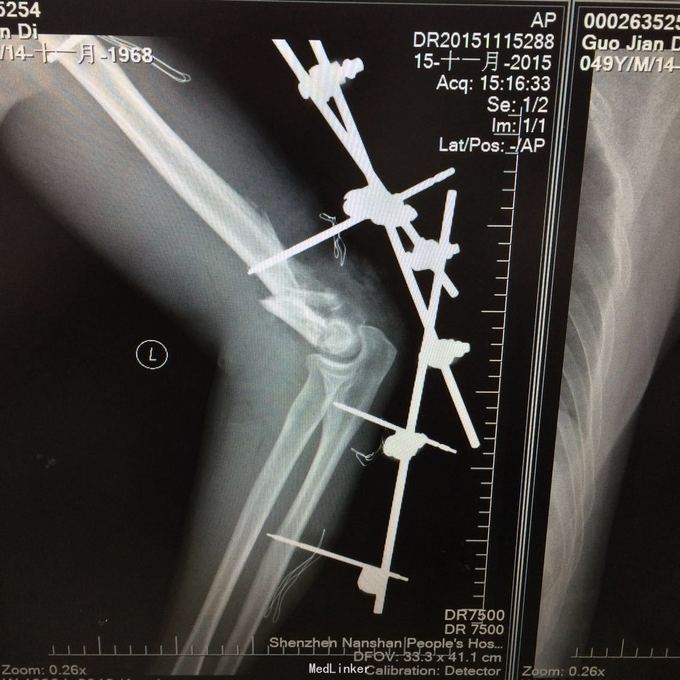

1、左肱骨远端粉碎性开放性骨折;2、左肘关节半脱位;3、左手第4、5掌骨远端骨折;4、右手第1、3、4远节指骨骨折;5、右手第5中节、远节指骨骨折;6、鼻部软组织挫裂伤;鼻中隔骨折;7、右侧第3--7肋骨折;8、左跟骨粉碎性骨折;9、左眉弓软质挫裂伤;10、左肺挫伤;11、脑震荡。 1.完善三大常规、PT四项、生化等各项常规检查; 2.完善CT检查,予抗破伤风、抗感染、镇痛、止血等对症支持治疗; 3.请口腔、耳鼻喉、眼科等相关科室会诊; 4.请示上级医师,指导下步治疗。 手术时间:2015年11月15日 术后诊断:左肱骨远端开放性粉碎性骨折 麻醉方式:全身麻醉 手术名称:左肱骨远端开放性粉碎性骨折清创缝合外固定架固定术 手术时间:2015年12月25日 术后诊断:左肱骨远端粉碎性骨折 麻醉方式:臂丛麻醉 手术名称:左肱骨远端粉碎性骨折切开复位内固定术 。 手术时间:2015-12-3 术后诊断:左跟骨粉碎性骨折;左肱骨远端粉碎性开放性骨折;左肘关节半脱位;左手第4、5掌骨远端骨折;右手第1、3、4远节指骨骨折;右手第5中节、远节指骨骨折;右足拇趾撕脱骨折并趾间关节脱位;鼻部软组织挫裂伤;鼻中隔骨折;右侧第3--7肋骨折;左眉弓挫裂伤;左肺挫伤;脑震荡。 麻醉方式:腰硬联合 手术名称:左跟骨粉碎性骨折切开复位钛板内固定术